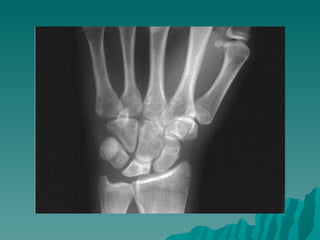

Keinböck hastalığı

 Genellikle

yetişkinlerde ve

unilateral

 El bileğinde ağrı ve

hassasiyet

r          Travmalar ve

tekrarlayan

mikrotravmalar

Rober Kienböck (1871 -1953)     suçlanır.

 X-Ray: lunat kemikte

yaygın opasite

kemikte yassılaşma,

fregmantasyon

Keinböck hastalığı  Genellikle yetişkinlerde ve unilateral  El bileğinde ağrı ve hassasiyet r  Travmalar ve tekrarlayan mikrotravmalar Rober Kienböck (1871 -1953) suçlanır.  X-Ray: lunat kemikte yaygın opasite kemikte yassılaşma, fregmantasyon